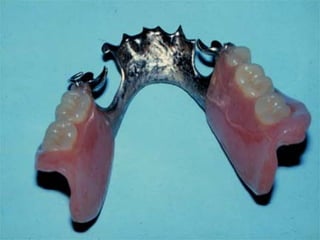

Removable partial denture:

Any prosthesis that replaces some teeth in a

partially edentulous patient and can be

removed from the mouth by the wearer.